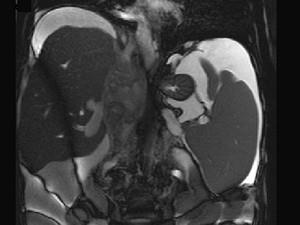

问题 女性,26岁,腹胀不适7月,腹软,肝右肋缘下1cm,影像检查如图,可能的诊断为 ( )

选项 A、布加综合征 B、脂肪肝 C、原发性肝癌 D、肝硬化腹水 E、肝血管瘤

答案 A